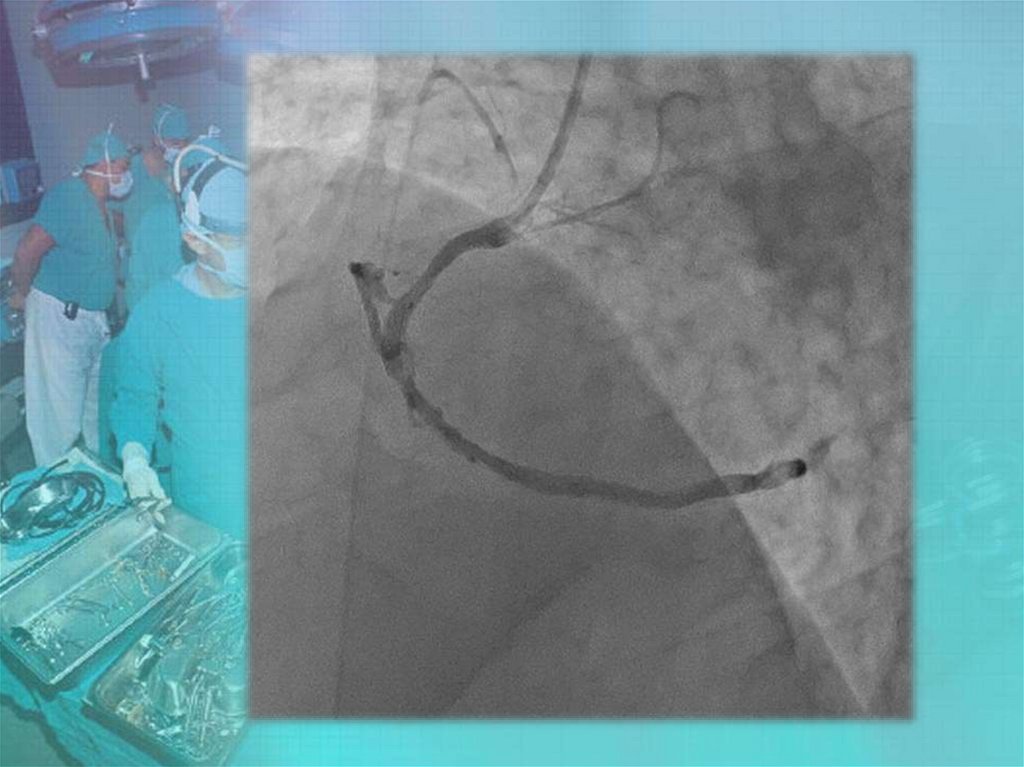

Коронары. СНК кафедры факультетской хирургии №2 лечебного факультета